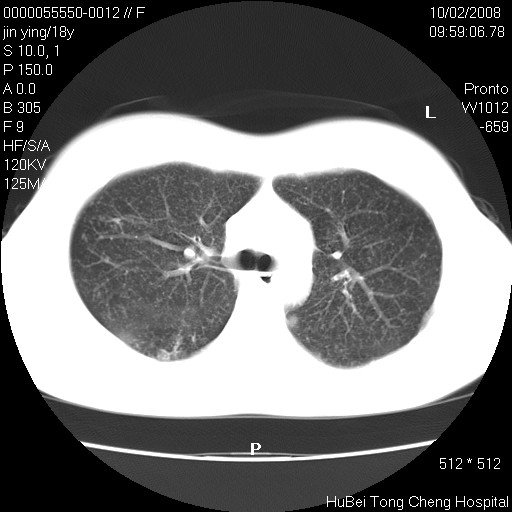

患者 女,18y。发热十余天,伴咳嗽。pe:t39⒈℃,bp 110/80mmhg,p 86次/min。神清,精神欠佳。双肺可闻及少许湿罗音。既往史不详。

临床诊断:肺部感染?

胸部ct轴位平扫(层厚10mm,螺距1.5,重建间隔10mm),图像如下: